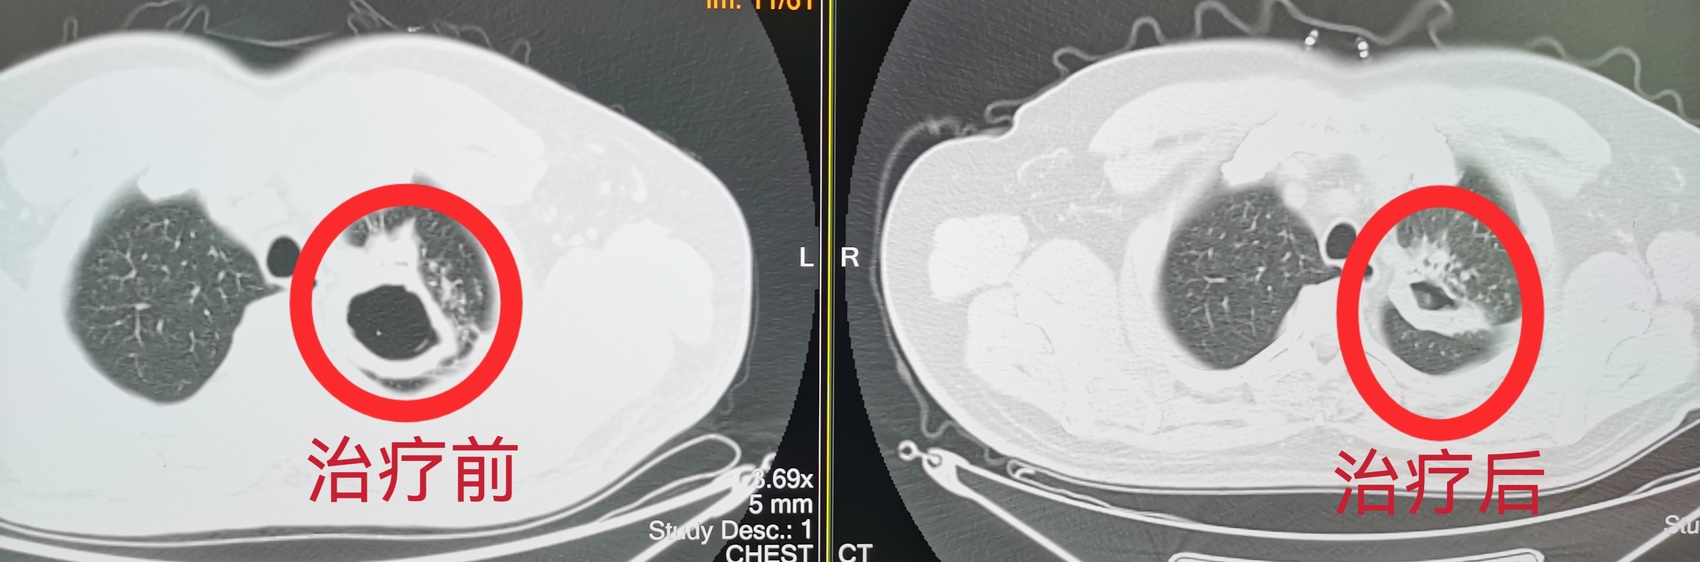

治疗前后空洞对比

一张在基层卫生中心拍的CT,被远程系统实时传至资阳市中心医院。影像专科医生敏锐识别出疑似肺结核病灶并及时反馈,患者叶先生迅速转入资阳市中心医院接受专科规范治疗,之后转入家门口的基层医院继续进行康复。叶先生的这次就医经历,正是资阳借助“云端”力量,让优质医疗资源跨越地域阻隔,直接服务基层患者的一个缩影。

“远程影像不仅是技术的联通,更是诊疗闭环的构建与分级诊疗的落地实践。”资阳市中心医院相关负责人表示。该服务使得疑难病例能及时上转明确诊断,如发现肺结核、疑似肿瘤或脑血管异常等复杂情况后,可迅速引导患者进入上级医院进一步检查与治疗;而当诊断明确、病情稳定后,患者又可带着方案返回当地随访复查,实现了“基层首诊、上下联动”的高效医疗服务闭环。